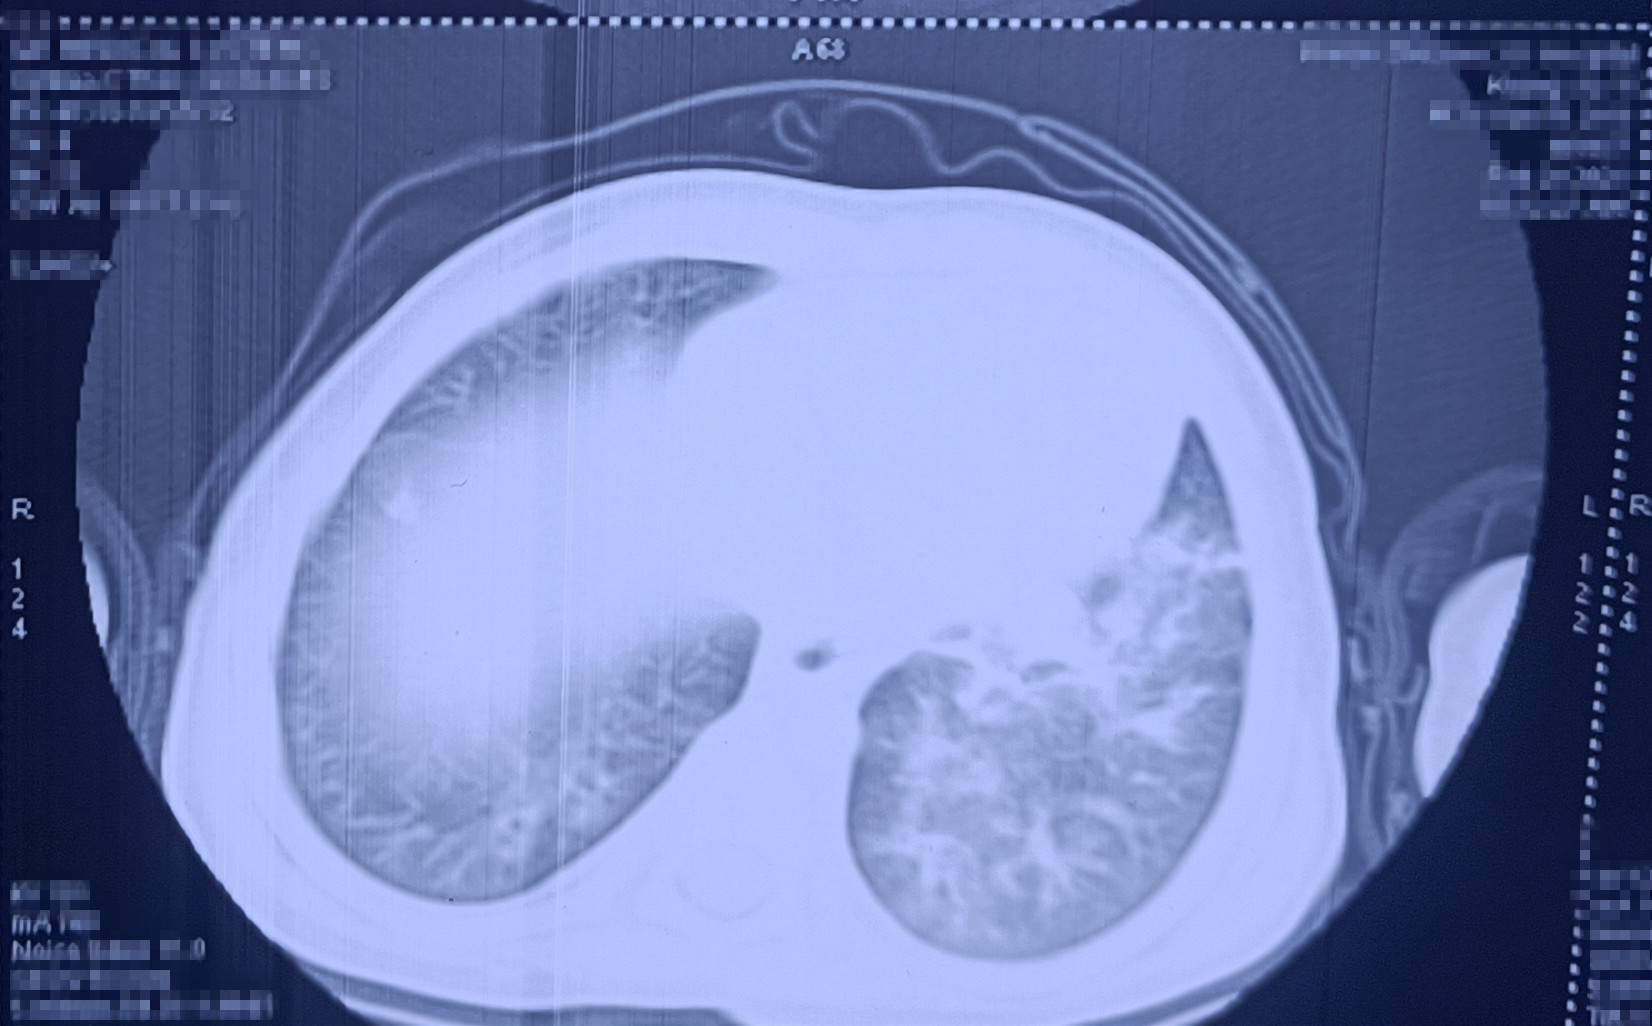

CT结果显示明明肺部感染严重

呼吸介入科主任黄寒立即查看明明情况,这时的明明发高烧、呼吸急促费力,且烦躁不安,结合临床病史及影像资料,考虑溺粪后感染严重,易引发急性负压性肺水肿导致病情进一步恶化,紧急予以床旁行急诊儿童支气管检查、无创呼吸机辅助呼吸等。经过医护人员的紧急救治、积极抗感染等对症支持治疗及精心护理后,孩子终于渡过危险期,病情逐渐稳定下来,并于3月8日顺利出院。